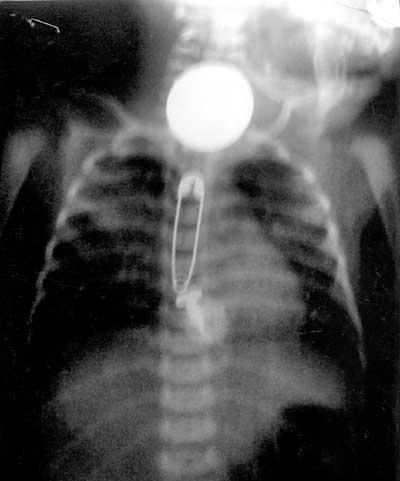

১২ দিন বয়সের মেয়ে শিশূ বমি, জ্বর আর স্বাসকস্ট নিয়ে ভত্তি হলো হাসপাতালে। এক্সরে করে পাওয়া গেলো উপরের খাদ্যনালীতে একটি কয়েন, একটি সেপটিপিন আর একটি স্ক্রু। আর পেটের মধ্যে আরও কিছু জিনিশ। পরে এক এক করে বের হলো

কয়েন

সেপটিপিন

স্ক্রু

তুলার বল

পলিথিনের টুকরা

৪টি কাচের টুকরা।

যদিও শিশুটির

যদিও শিশুটির অভিবাবক মেয়েটিকে মুখে কিছু খাওয়ায়নি বলে জানিয়েছে তারপরও পুলিশের তদন্ত্র চলছে। ঘটনাটি ঘটেছে রাজস্থানের একটি গ্রামে।